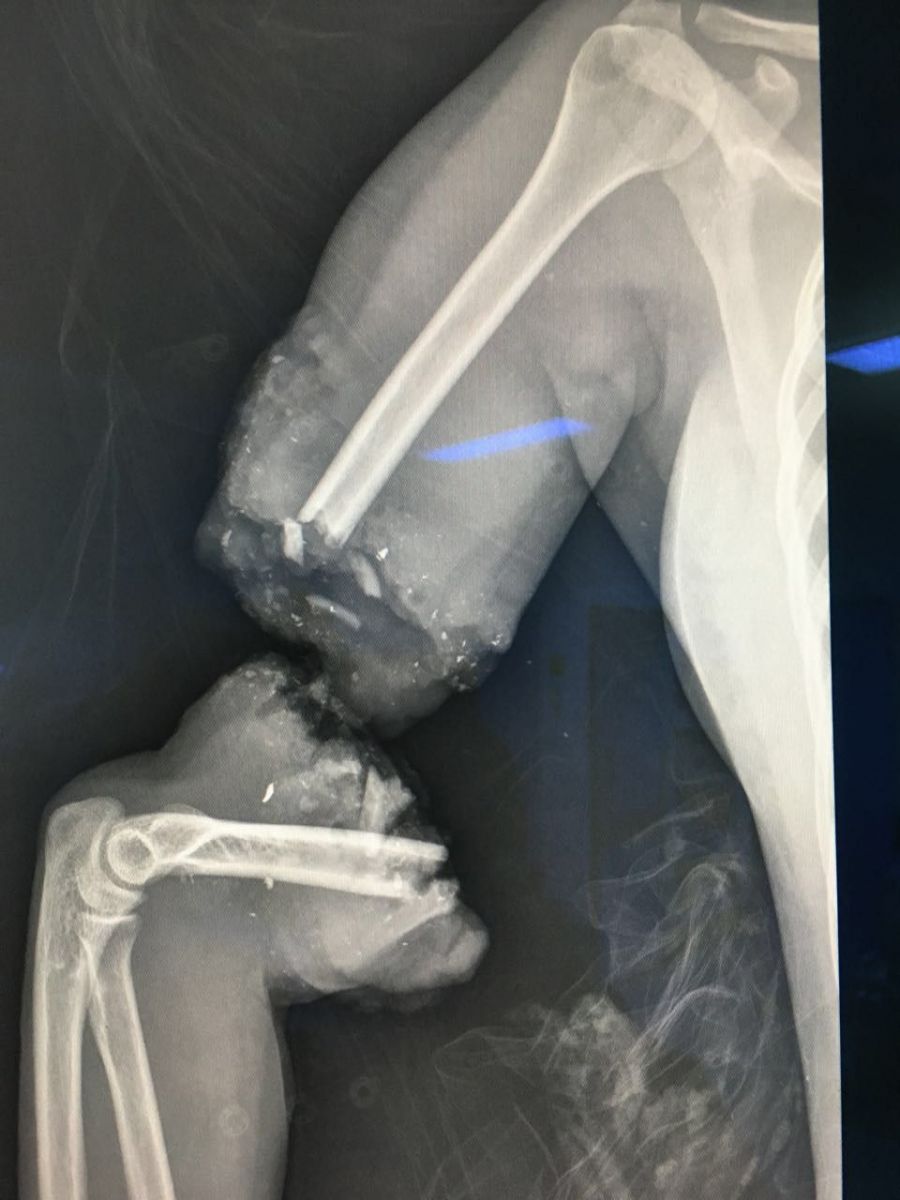

تمكن فريق جراحي بمستشفى الملك عبدالعزيز في جدة (غرب السعودية) الثلاثاء 27 سبتمبر من إنقاذ سيدة حامل وجنينها بعد تعرضهم لحادث دهس خطير أثناء عبور أحد الشوارع المزدحمة، ما أدى لبتر ذراع الأم بالكامل.

وأوضحت الصحة السعودية أن المريضة حضرت إلى طوارئ المستشفى كحالة حرجة تستدعي إنقاذ الأم والجنين، وعلى الفور جرى تشكيل فريق طبي للتعامل مع الحالة، وتم إجراء عملية جراحية عاجلة لترميم الأعضاء المبتورة في عملية استغرقت 6 ساعات متواصلة، انتهت بإعادة اليد إلى وضعها السابق.